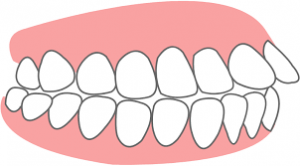

①上顎前突

上顎前突とは上の前歯や上あごが下の歯よりも前方にでていることをいいます。

大きく二つに分類すると上の歯の傾斜によって前に出ている歯自体のものと、下の歯に比べて上の歯全体が大きく、上の歯茎と歯が前方にでている骨格的なものに分かれます。

上の歯の傾斜によって前歯が出ている場合の原因は様々ですが、幼少期の指しゃぶりや舌で上の前歯を押す癖によって起こりやすいと言われています。

また鼻呼吸ではなく口呼吸をしている場合も歯が前に出てきてしまいます。

口呼吸になるとお口の中が乾燥しやすくなり、歯周病や虫歯のリスクが高くなるだけではなく、口臭の原因にもなります。

治療していく方法は様々ですが、表側矯正・裏側矯正・インビザラインなどで歯を正しい位置に移動させるのが一般的です。

上顎前突は日本人で2番目に多い不正咬合となっています。